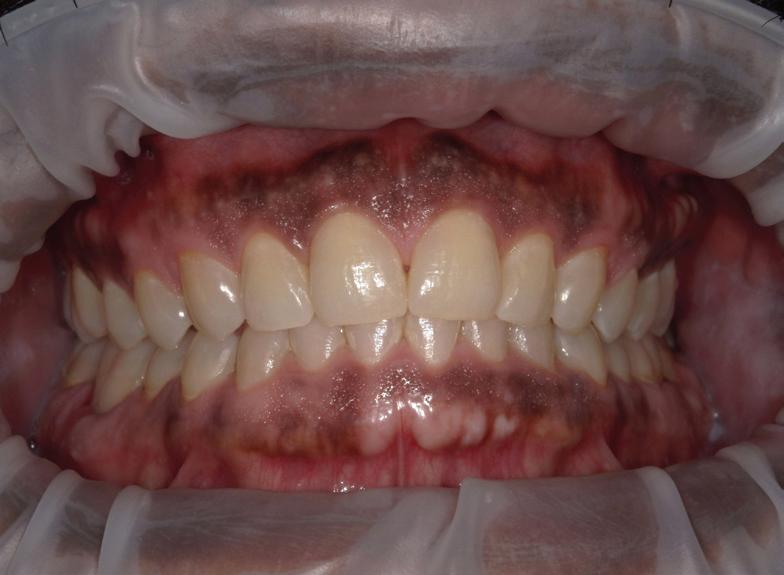

By Karl A. Smith, DDS, MS

Lasers have long been the standard of care in medicine for many surgical and cosmetic procedures. Lasers are used for vision correction, wrinkle and hair removal, vein therapy, and anti-aging treatments.

In the world of dental care, advancements like laser dentistry and laser periodontal therapy are not just technological leaps; they are helping find new ways to improve overall body health and well-being including how mental thoughts affect oral conditions.

For many, a visit to the dentist can evoke feelings of anxiety and discomfort. However, the advent of laser-based treatments has begun to transform these perceptions, offering a gentler, more reassuring experience.

Laser dentistry, with its precision and minimally invasive approach, has become a beacon of comfort for patients. This modern technique, using focused light beams, allows dentists to perform various procedures with minimal impact on surrounding tissues.

For patients, this precision translates to less pain and quicker recovery. The emotional relief provided by laser dentistry is profound. Patients who once felt anxious at the mere thought of a dental drill now find solace in the quiet, gentle hum of the laser. The reduced need for anesthesia and the minimal bleeding during procedures further alleviate fears, creating a more relaxed and comfortable dental experience.

Treating gum disease, a common and often distressing condition, has become much less daunting. Patients undergoing laser periodontal therapy report not only

physical ease but also a sense of emotional relief. They feel reassured, knowing that the treatment is thorough yet conservative, targeting only the diseased areas while preserving healthy gum tissue.

This results in the best outcome for the patient because the teeth remain covered with pink, healthy gum tissue instead of being “long and ugly.” Patients can quickly recover with few or no

sutures (stitches) and very little discomfort. This is a dramatic improvement over older periodontal treatment techniques where a lot of good gum and bone was removed to “reduce pockets.”